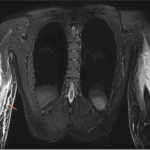

説明後, 救急外来に降りました. 脳外科の診察はすでに終了していて, 頭部打撲傷でした. 腰を痛がっているので, 診察したところ, 背骨(胸椎)と腰の骨(腰椎)と骨盤の骨(仙骨)を圧すと痛がるので, 骨折を疑って, X線写真とMRIを撮像するようにオーダを入れました.

新鮮な骨折(骨折してから概ね2-3カ月以内)では, MRIで椎体が白く写りますが(上図B), 旧い骨折(骨折してから概ね4カ月以上経過)では, 椎体が潰れていても(上図C), MRIでは椎体が白く写らずに, 骨折のない椎体と同じような色合いに写るようになります(上図D).

撮像されたX線写真を見たところ, 胸椎と腰椎が3箇所で潰れて骨折していましたが, MRIでは骨折の所見がなく, 数ヶ月以上前の旧い骨折であると診断しました. 骨盤の骨にも異常はなかったので, 打撲傷と診断して, 鎮痛薬を処方して, 帰宅していただきました.